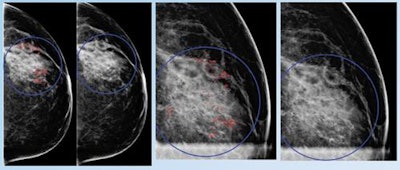

Early breast cancer was flagged by the CAD software three years prior to biopsy and showed a progressive increase in quantitative score over the three years. All images courtesy of Dr. Alyssa Watanabe.

Early breast cancer was flagged by the CAD software three years prior to biopsy and showed a progressive increase in quantitative score over the three years. All images courtesy of Dr. Alyssa Watanabe.In other results, the researchers found that progressive deep-learning training continued to improve the performance of the CAD software over time for breast masses.